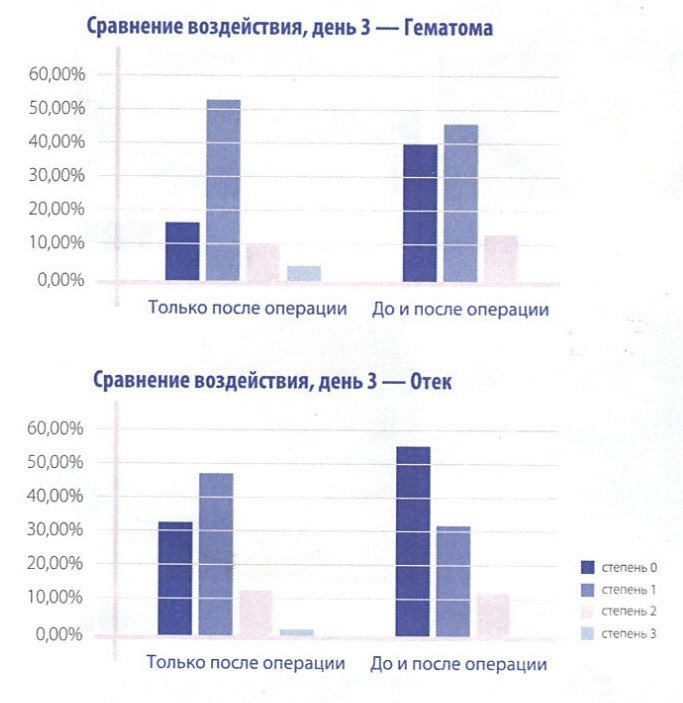

Уменьшение отечности и синяков. После блефаропластики и ринопластики отечность и синяки могут быть распространенными. INDIBA может помочь ускорить устранение отечности и уменьшить синяки, благодаря своей способности улучшать кровообращение и лимфодренаж.

Одной из ключевых особенностей аппарата INDIBA является способность работать в режиме субтермии (низкотемпературный режим), что позволяет врачам начинать обрабатывать зону хирургического вмешательства прямо в день операции. Это способствует более быстрому заживлению и снижению отечности, что особенно важно после пластических вмешательств.Безопасность и комфорт